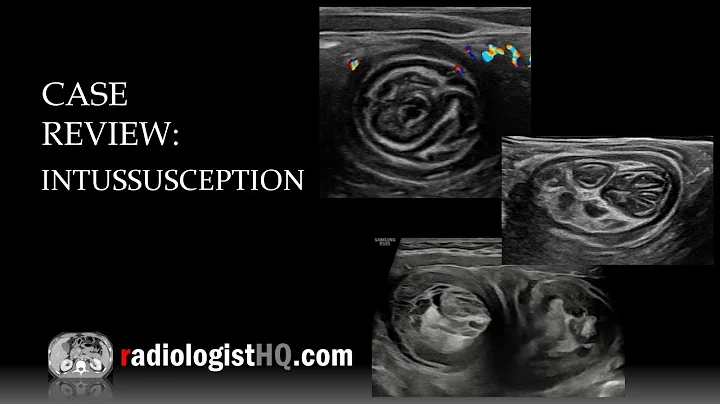

Invagination ! In Ultrasound

suitable for all #residents an medical doctor even how loves knowledge :) have a question?? comment please and ...